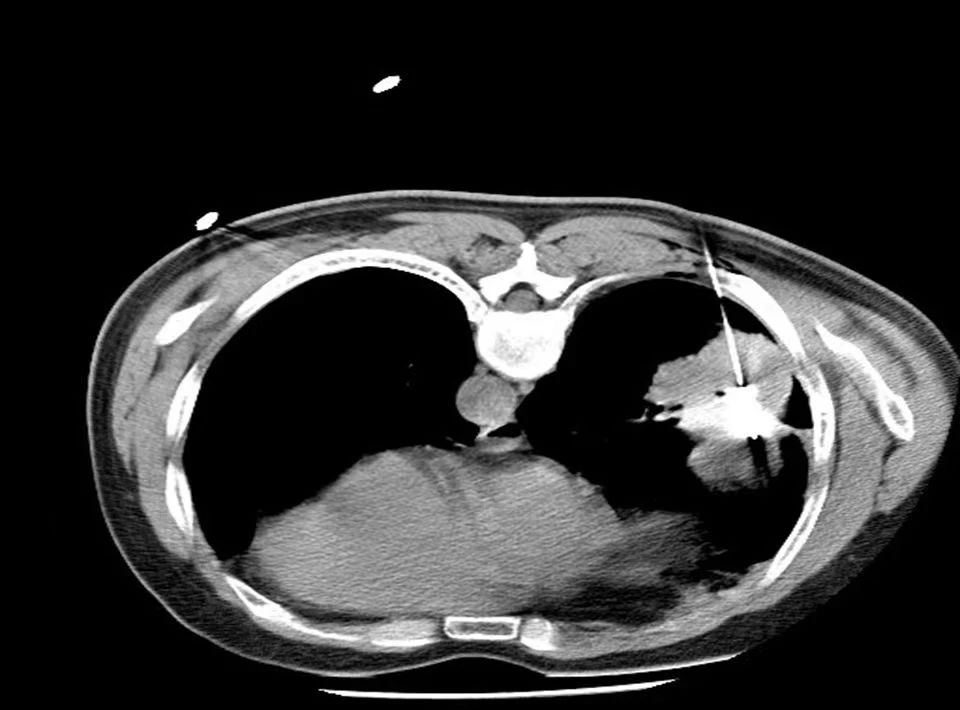

微波消融手术病例 患者张大爷,85岁,肺占位性病变(左下肺)约1.1cm,伴有心脏病、高血压,一年前体检时无意中发现左下肺有一约3mm大小磨玻璃结节...